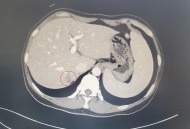

网络资讯患癌肝被肿瘤占近半,胆囊癌症转移肝脏有治吗?大家好,今天小编关注到一个比较有意思的话题,就是关于患癌肝被肿瘤占近半的问题,于是小编就整理了1个相关介绍患癌肝被肿瘤占近半的解答,让我们一起看看吧。胆囊癌症转...发布时间:2025年10月09日立即查看 -

网络资讯患癌肝被肿瘤占近半,当癌症转移时,它通常会先转移到肝脏,为何癌细胞容易转移到肝脏?大家好,今天小编关注到一个比较有意思的话题,就是关于患癌肝被肿瘤占近半的问题,于是小编就整理了1个相关介绍患癌肝被肿瘤占近半的解答,让我们一起看看吧。当癌症转移...发布时间:2025年10月09日立即查看 -

网络资讯患癌肝被肿瘤占近半,肝的恶性肿瘤长在肝里面是不是比长在表面更危险?大家好,今天小编关注到一个比较有意思的话题,就是关于患癌肝被肿瘤占近半的问题,于是小编就整理了2个相关介绍患癌肝被肿瘤占近半的解答,让我们一起看看吧。肝的恶性肿...发布时间:2025年10月08日立即查看 -

网络资讯患癌肝被肿瘤占近半,癌症转移到肝能活多久?大家好,今天小编关注到一个比较有意思的话题,就是关于患癌肝被肿瘤占近半的问题,于是小编就整理了2个相关介绍患癌肝被肿瘤占近半的解答,让我们一起看看吧。癌症转移到...发布时间:2025年10月08日立即查看 -

网络资讯患癌肝被肿瘤占近半,肝癌占肿瘤致死原因第几位大家好,今天小编关注到一个比较有意思的话题,就是关于患癌肝被肿瘤占近半的问题,于是小编就整理了1个相关介绍患癌肝被肿瘤占近半的解答,让我们一起看看吧。肝占位,是...发布时间:2025年10月08日立即查看